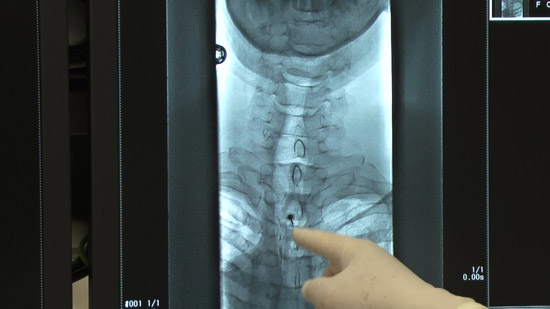

(2)穿刺部を透視画面と合わせて確認し、位置決めを行う。

(4)抵抗消失法にて硬膜外穿刺を行う、透視画面で確認。

※造影剤を注入し更に確認。同時に確認画像を撮影。